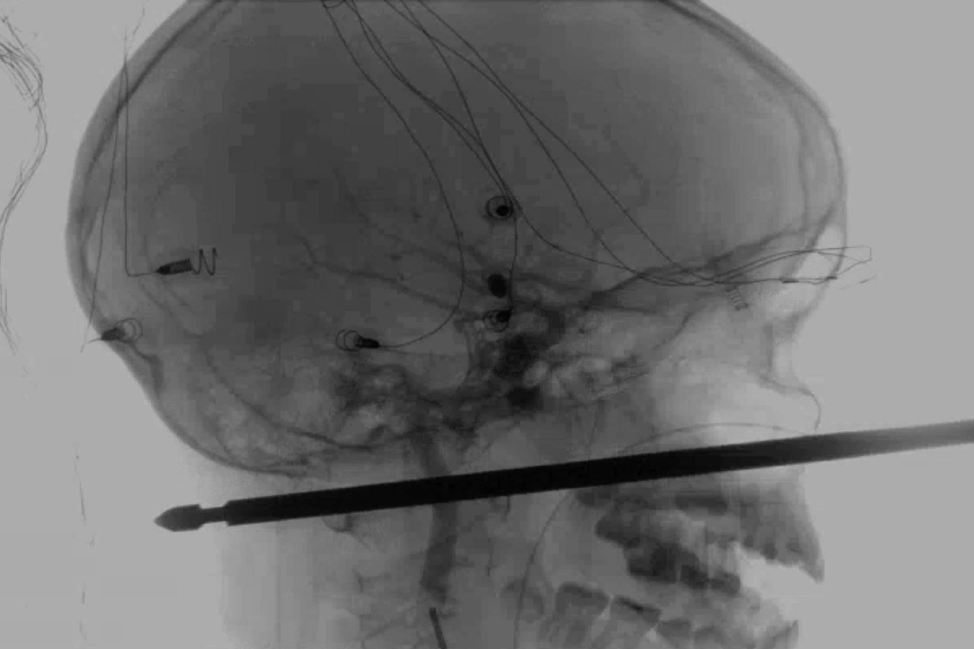

El pincho le entró por la mejilla a la altura de la nariz y le salió por la nuca, pero no le tocó los ojos, ni la médula espinal ni ningún vaso sanguíneo, según detalla el diario The Kansas City Star. Koji Ebersole, director de neurocirugía endovascular en el Hospital de la Universidad de Kansas, donde se le sometió a una operación de alto riesgo para extraer el utensilio el pasado fin de semana, explica al diario que en «uno entre un millón de casos» un objeto punzante penetra «13 o 15 centímetros por la cara hasta la parte trasera [de la cabeza] y no toca» ningún punto clave.

La forma del pincho, según los médicos, añadía una dosis extra de peligro a la operación, ya que no era redondo como la mayoría sino cuadrado y con bordes afilados. Tenía que salir completamente recto, tan limpiamente como había entrado, ya que torcerlo podía causar lesiones severas, posiblemente mortales.